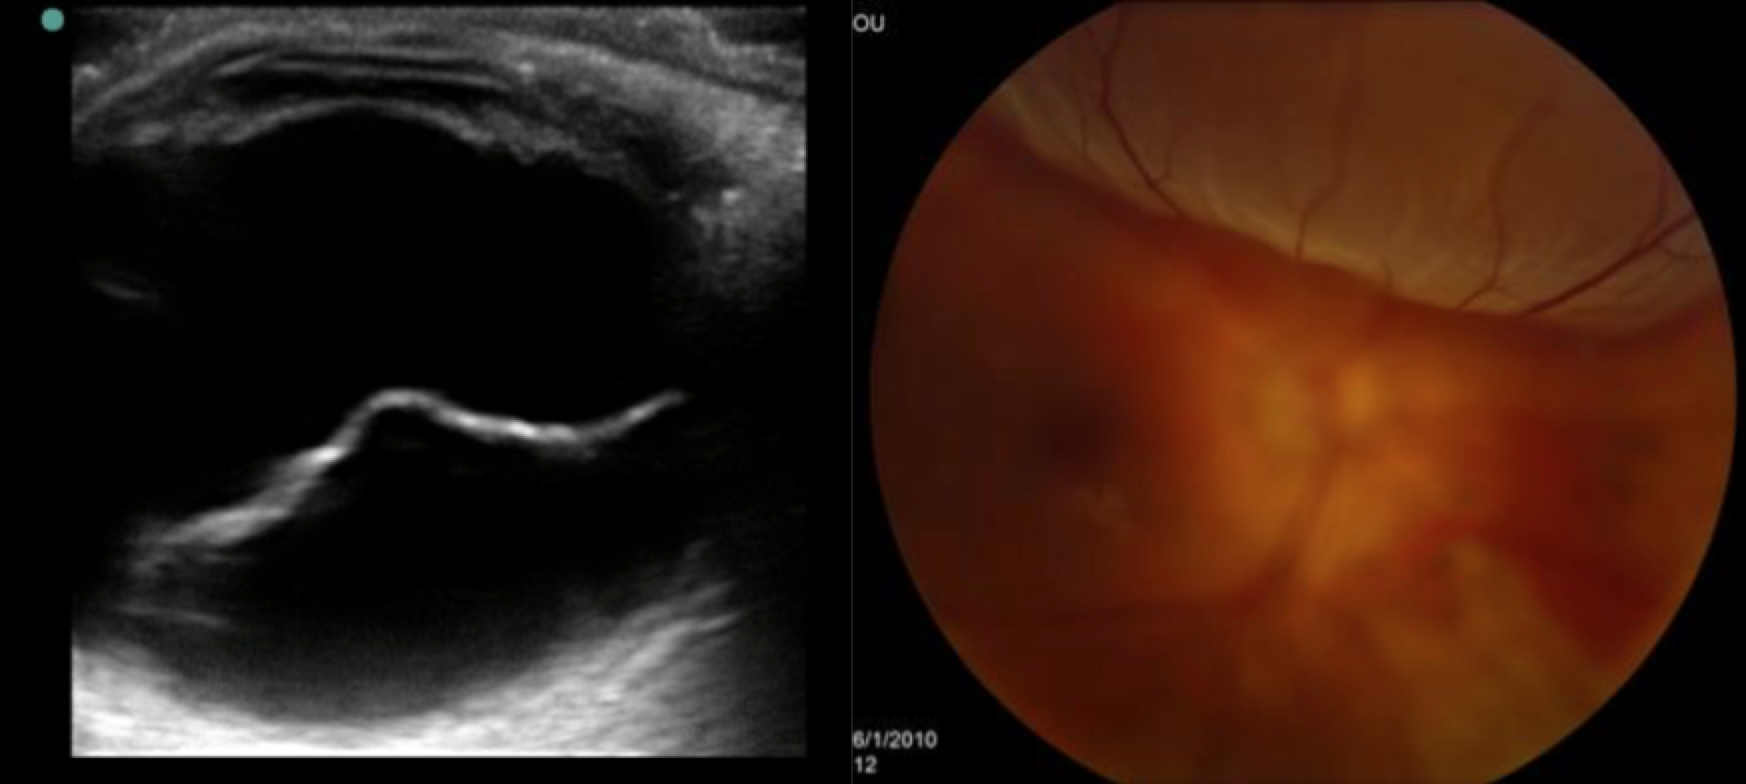

- Retinal detachment can occur in the setting of trauma but is often not associated with an instigating event. Three mechanisms exist: rhegmatogenous (most common), exudative, and tractional. Sudden onset of new floaters, black dots, and flashes of light are common symptoms. Early stages may present with visual field loss, but if the macula or central retina becomes involved, visual acuity is severely affected. This is not painful. Afferent pupillary defect may be present, but no signs of red eye will be present. US will be the key to diagnosis, which will demonstrate a highly reflective, mobile undulating membrane. Treatment requires emergent ophthalmology consultation and evaluation.1-3,16,18,21

US (left) and fundoscopy (right) of retinal detachment. Images from http://emedicine.medscape.com/article/798501-overview

Patient 2: A quick bedside US confirms retinal detachment. Ophthalmology is consulted.